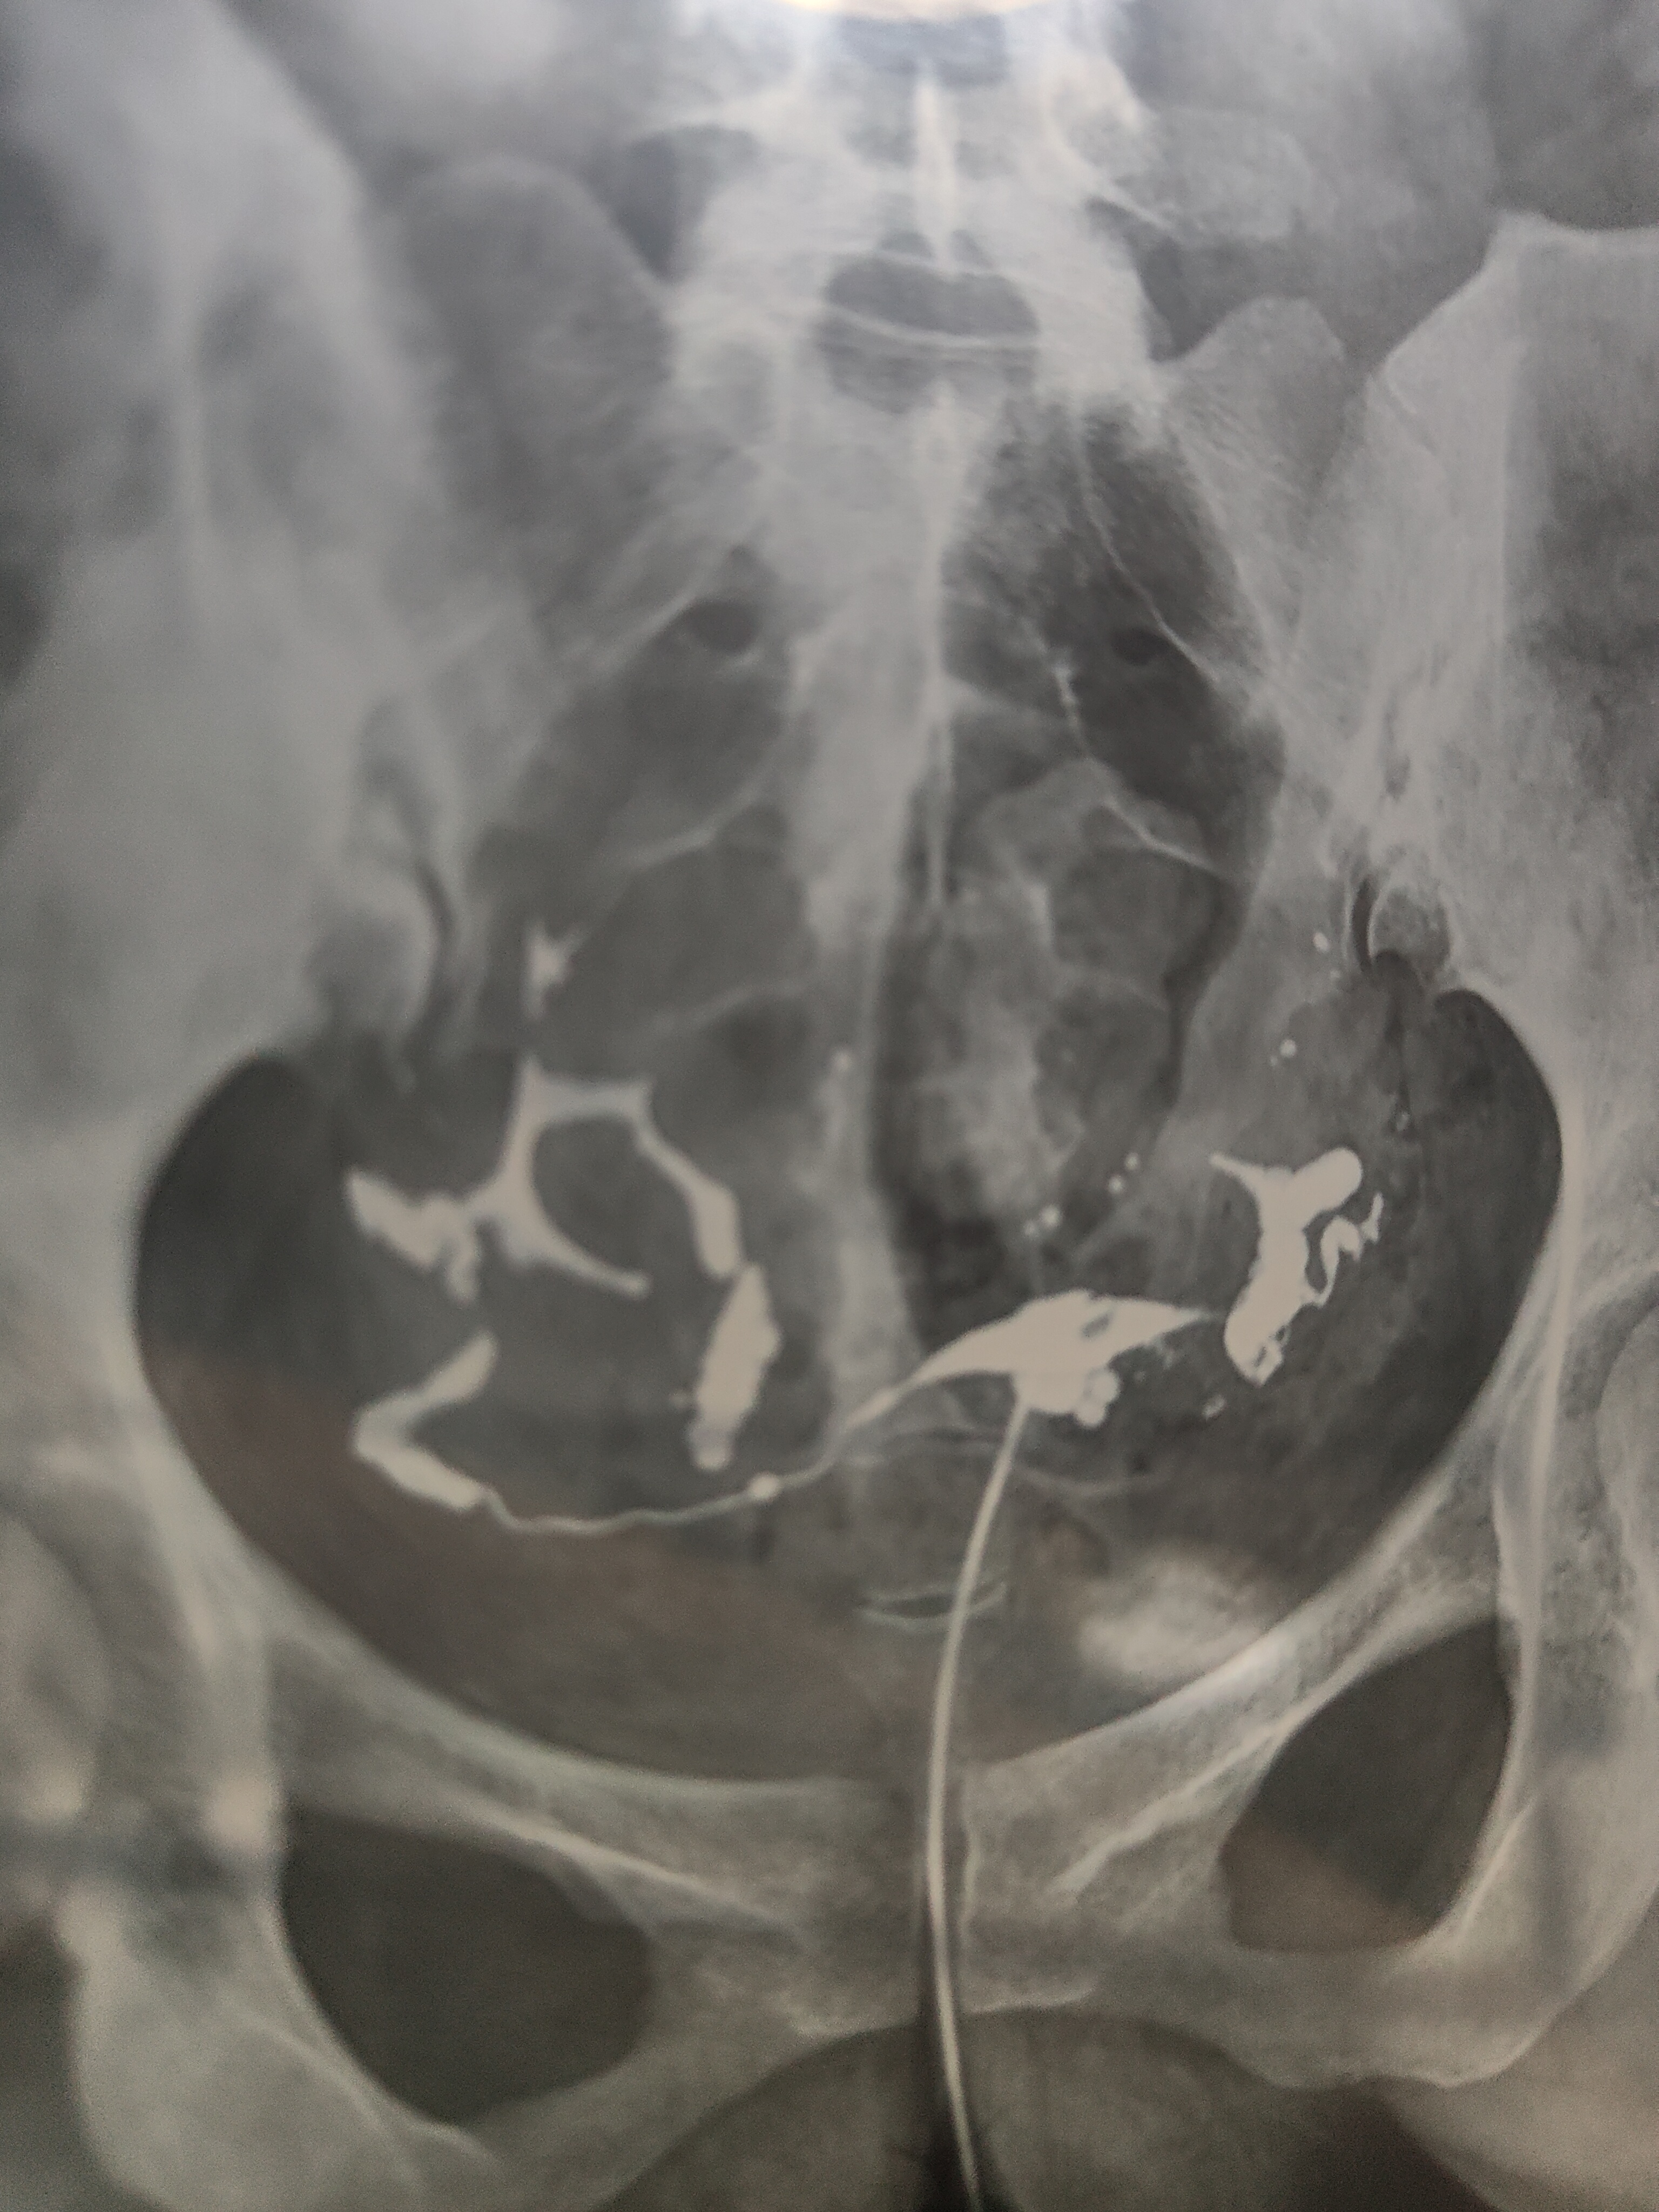

各位医生好,,前天做了输卵管造影,请帮忙看看这些造影片是正常的么?

双侧输卵管通畅,弥散好,正常造影,可以试孕。

你好,结果正常,放心吧,祝好孕。